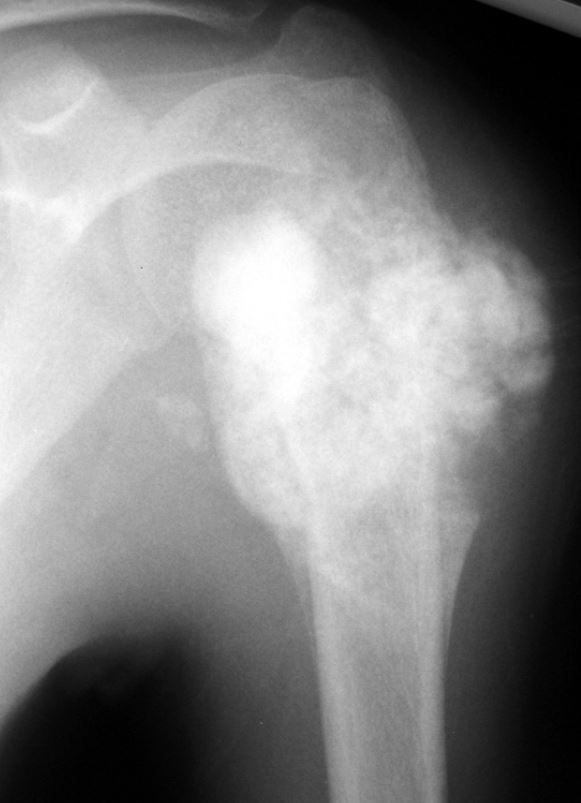

The type of fracture AND the bone that is fractured

Spiral and Humerus